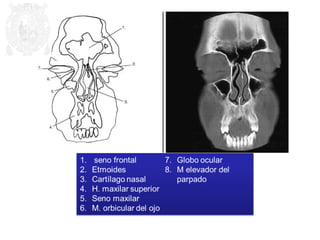

1. Celdillas etmoidales

2. N. óptico

3. M. recto externo

4. Seno esfenoidal

5. Celdillas mastoideas

6. B

7. Pabellón auricular

8. Conducto auditivo externo

9. Globo ocular

10.M. recto interno